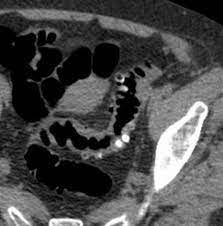

Colon cancer can become secondarily infected and simulate sigmoid diverticulitis,. But when they do show up, the symptoms can mimic those of crohn's disease. It does not appear that diverticulitis and cancer are heavily linked, as the former is a very common condition that is generally easily treated. Went for a ct before a surgery could be scheduled for scar tissue in my abdomen. Colon cancer however is caused by small lumps that progress into cancerous tumors.

In the retrospective part of the study, 27 patients were diagnosed with diverticulitis and 31 were diagnosed with colon cancer. It does not appear that diverticulitis and cancer are heavily linked, as the former is a very common condition that is generally easily treated. Patients who present with acute diverticulitis may have significant abdominal pain and fever, which may be confused with inflammatory bowel disease or peptic ulcer disease. Diverticular disease and the risk of colon cancer. I thought i may have ovarian cancer from all the symptoms, which are painful left abdominal pain, lower backache which is constant, pain in groin and down left leg, fever and then chills, very fatigued to the point of dragging myself through the day, constipation, frequent and urgent need to urinate and now nauseus as well. When colonic obstruction is present, colon cancer is more likely than diverticulitis. Colon polyps are growths on the inner lining of the colon, and diverticulitis happens when a diverticulum ruptures and becomes infected. The most frequent issues with the bowel or colon, affect the colon's ability to work properly. However, people with diverticulitis may be at higher risk of developing colon polyps. Colon polyps do not cause diverticulitis. Screening for colon cancer can detect and remove precancerous polyps before they have the chance to develop into cancer. I had 10 or 12 inches of colon removed. Went for a ct before a surgery could be scheduled for scar tissue in my abdomen.

Does anybody know if they can tell the difference between diverticulitis and colon cancer on a ct scan? During diverticulitis, diverticula become infected or inflamed. Although at first diverticulitis and colon cancer may present similar symptoms, they are two very different conditions. Primary colonic gi lymphomas (usually diffuse large b cell), however, can be mistaken for ibd on colonoscopy. Most times it occurs when small pouches called diverticula become infected or swollen.

Diverticulitis is a condition set off by infection or rupture of diverticula,. Sure, a ct scan can be consistent with diverticulitis, but many other conditions can precisely mimic this ct scan appearance. I was diagnosed with diverticulitis with a severe infection; It does not appear that diverticulitis and cancer are heavily linked, as the former is a very common condition that is generally easily treated. Symptoms of diverticulitis and colon cancer may include abdominal pain. The most frequent issues with the bowel or colon, affect the colon's ability to work properly. August 8, 2009 at 12:09 pm. Yes diverticulosis is benign, has distinct appearance from ca on ct for a trained radiologist will read as accurate as reading finger prints, some times in between diverticula the wall may be thickened, may have mucosal overgrowth will mimic a early cancer, then colonoscopy indicated, at 39 cancer is not common but age is not exception for ca, ask again for referral. Diverticulitis involves common digestive tract growths called diverticula. Screening for colon cancer can detect and remove precancerous polyps before they have the chance to develop into cancer. Patients who present with acute diverticulitis may have significant abdominal pain and fever, which may be confused with inflammatory bowel disease or peptic ulcer disease. When colonic obstruction is present, colon cancer is more likely than diverticulitis. Although at first diverticulitis and colon cancer may present similar symptoms, they are two very different conditions.